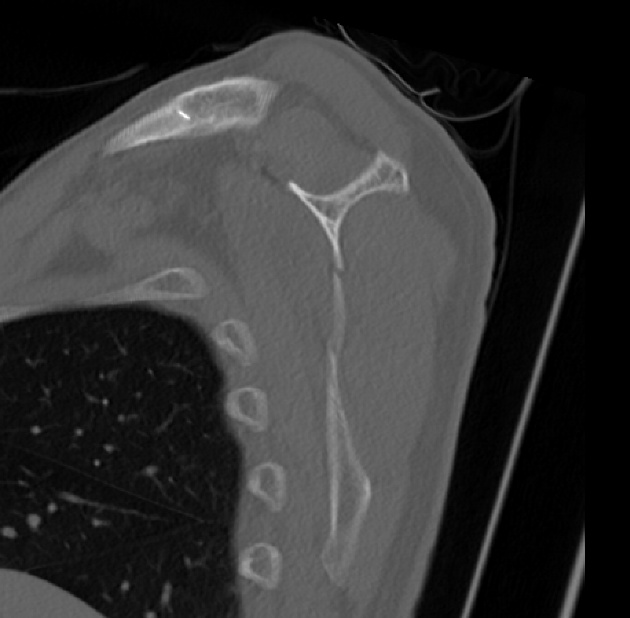

2022.06.07 CT SCAN

- M/50대

- fall down

- X-Ray 검사 상 견갑골 골절의심 됨

- Axial Scan 후 MPR로 Axial, Coronal, Sagittal image Recon 함

- Rib CT 포함하여 검사함.

3.Finding.

4.conclusion

mildly displaced fracture of body of scapula.